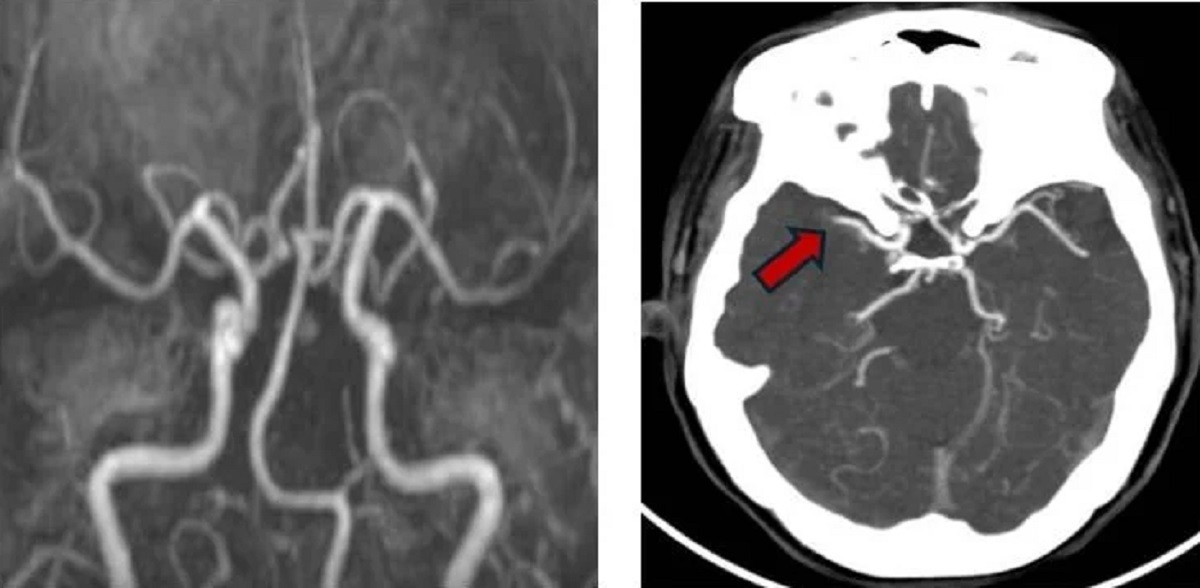

| Hình ảnh mạch máu của bệnh nhân được tái thông nhờ thuốc tiêu sợi huyết nhưng sau đó lại bị tắc nghẽn bởi cục máu đông ở lần đột quỵ thứ hai (ảnh: BVCC) |

Ngay lập tức, quy trình “báo động đỏ” nội viện được kích hoạt. Trên kết quả chụp CT mạch máu não, bác sĩ ghi nhận tình trạng tắc động mạch não giữa bên phải – kèm hình ảnh huyết khối mới hình thành. Người bệnh được đưa thẳng vào đơn vị can thiệp mạch máu thần kinh để nhanh chóng tiến hành lấy huyết khối qua đường ống thông.